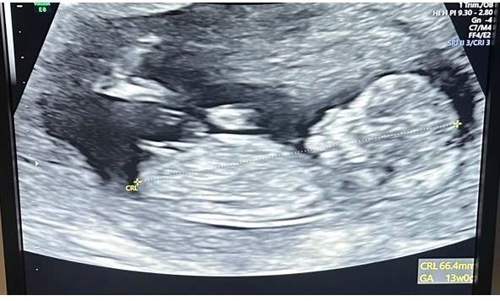

When I found out I was pregnant it was a very surreal experience because it had been 10 years. Anybody who goes through fertility challenges will get into a mindset of preparing for the worst. It was incredible and a very emotional experience.

It’s been a dream pregnancy. I'm so lucky and so grateful. This has been my first experience with pregnancy. The second three months I felt I could take on the world. I’ve had no health issues or problems.